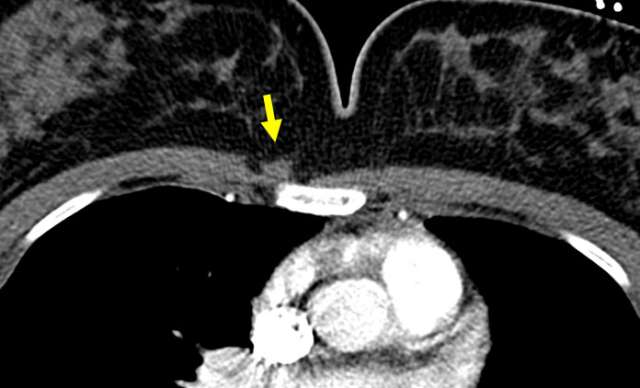

Magnetic Resonance Imaging and Computed Tomography Appearance

On MRI, the sternalis muscle demonstrates signal isointense to skeletal muscle. Likewise, CT scans depict the sternalis muscle as a well-demarcated structure with attenuation values similar to those of muscle, located anterior to the sternum. The shape is most often flat but can also be oblique or irregular (4). The presence of enhancing components on either MRI or CT is not typical and should prompt further evaluation or tissue sampling.